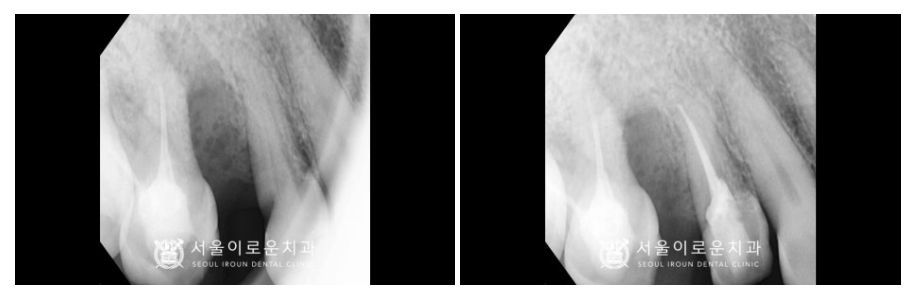

노란색 동그라미의

오른쪽 위턱 두 번째 작은 어금니(#15)의

뿌리 주변으로 잇몸뼈가

많이 흡수되어 있었으며,

충치도 심한 것을 확인할 수 있었습니다.

이 경우 살려 쓰기 어려울 것으로 판단되어

안타깝지만 발치가 필요한

상황이었습니다.

그리고 보라색 화살표의

오른쪽 위턱 첫 번째 작은 어금니(#14) 또한

통.증을 호소하셨는데요.

충치가 치아의 허리 부분에 해당하는

치경부 깊이 진행되어 있어

신경치료 후 크라운 치료가 필요하였습니다.

그리고 오른쪽 위턱 첫 번째

작은 어금니(#14)도

뿌리 끝까지 깔끔하게

신경치료를 마무리해 드렸습니다.